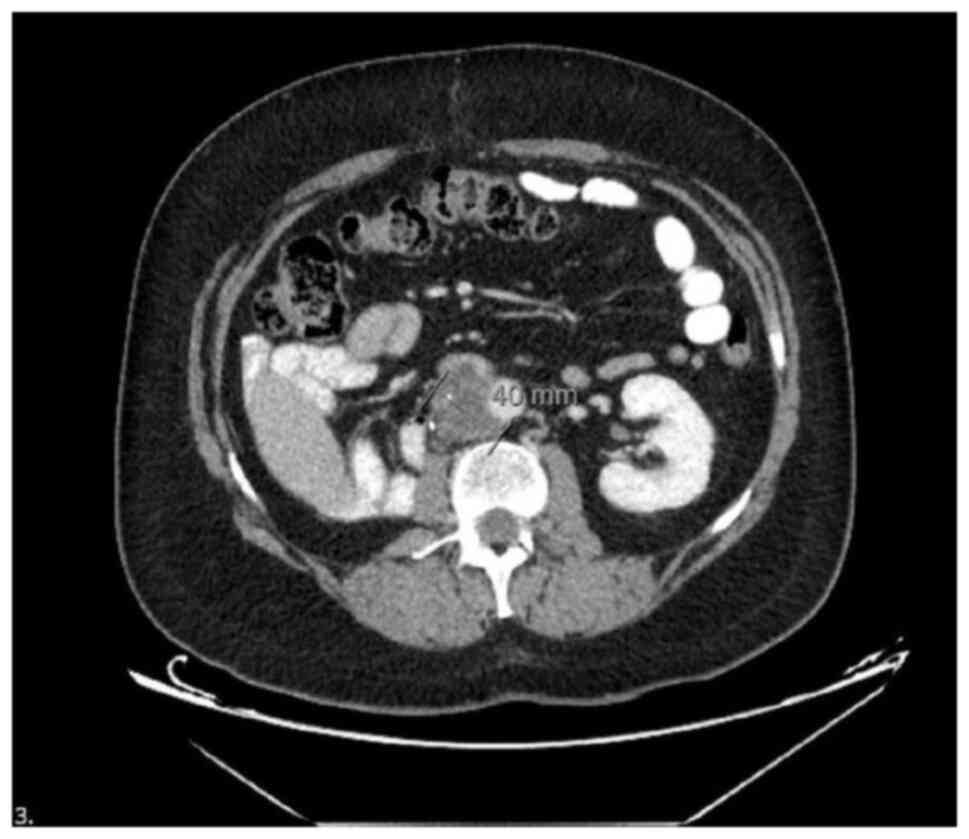

At 9 years post-operatively (November, 2013), the patient experienced AFP progression, prompting a CT scan of the thorax and abdomen, which again revealed a 2.5-cm retroperitoneal lymph node (it should be noted that only the reports of the CT images taken during this period are available for the patient. The actual images could not be obtained because they were performed at a private radiology laboratory in an external center). RPLND was performed, and the pathological examination was consistent with a mature teratoma. The immunohistochemical findings were as follows: AFP, positive; CD30, negative; PLAP, positive; OCT-4, negative; and D2-40, negative; this confirmed the diagnosis of a mature teratoma. Samples were obtained from different retroperitoneal lymph node regions during RPLND and were separately labeled and processed for histopathological evaluation. In the pathology report, samples 1 and 3 exhibited cystic structures lined with single-layered or cuboidal epithelium. Samples 2 and 4 revealed epithelial cysts and chondroid areas, which were consistent with the teratomatous component of the GCT. Samples 7 and 8 displayed areas of fat necrosis, thrombus organization, giant cells and inflammatory cell infiltration with vascular proliferation, which were interpreted as secondary changes. A reactive lymph node was dissected from sample 5. Sample 4 exhibited solid epithelial tumors along with cystic structures, and immunohistochemical analysis identified these as compatible with the solid yolk sac component of the tumor. All specimens contained only tumor tissue, with no surrounding lymphoid tissue. Of note, the pathological blocks were assessed at a private external laboratory by medical pathologists experienced in uro-oncology. Therefore, detailed visual and pathological data could not be provided. The information we share is based solely on the pathology report. The patient then received an additional four cycles of VIP chemotherapy between December, 2013 and March, 2014. Follow-up imaging performed 8 years later revealed new abdominal findings, including a 56 mm segment of a lobulated soft tissue mass in the pericaval region, reaching a size of 4 cm. The mass caused the obliteration of the vena cava lumen at the caudal level, with no contrast observed within the lumen, indicating venous compression and possible thrombosis. This vascular invasion led to bilateral lower extremity edema and venous stasis symptoms, requiring low-molecular-weight heparin therapy. These findings were compared with prior imaging reports from June, 2018, which revealed no such soft tissue mass. The current images revealed the development of recurrent lymphadenopathy (LAP) metastasis and vena cava invasion (Fig. 1).

Computed tomography image of the

retroperitoneal mucinous adenocarcinoma lesion arising from a

teratoma. Contrast-enhanced axial CT image demonstrating a

heterogeneous retroperitoneal mass with cystic and solid

components, consistent with teratoma-derived adenocarcinoma

following chemotherapy for relapsed testicular germ cell tumor. In

this CT image, the tumor along with a 40-mm lymphadenopathy (LAP)

complex that was developed as a result can be observed.

Figure 1

Computed tomography image of the retroperitoneal mucinous adenocarcinoma lesion arising from a teratoma. Contrast-enhanced axial CT image demonstrating a heterogeneous retroperitoneal mass with cystic and solid components, consistent with teratoma-derived adenocarcinoma following chemotherapy for relapsed testicular germ cell tumor. In this CT image, the tumor along with a 40-mm lymphadenopathy (LAP) complex that was developed as a result can be observed.